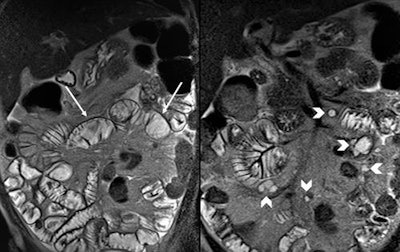

- In a patient with refractory celiac disease who has experienced recent deterioration of signs and symptoms, the presence of enlarged cystic mesenteric lymph nodes in addition to the typical findings of Celiac disease (fold reversal pattern) can help to make a diagnosis of cavitating mesenteric lymph node syndrome.